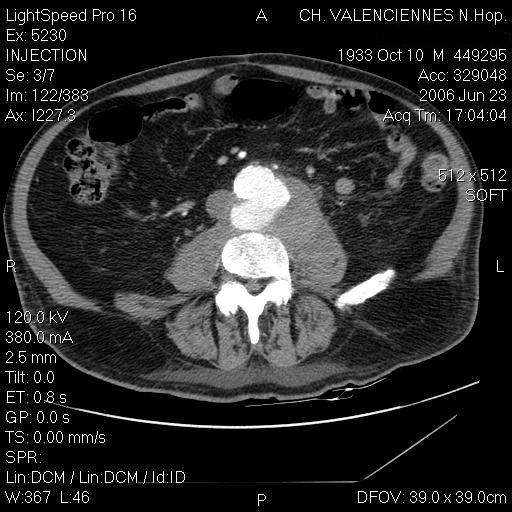

Spondylodiscitis and an aortic aneurysm due to Campylobacter coli.

Campylobacter coli is a rare cause of bacteremia. We report here the first case of C.coli spondylodiscitis complicated by an aortic aneurysm. Outcome was favourable with surgery and antibiotic therapy.